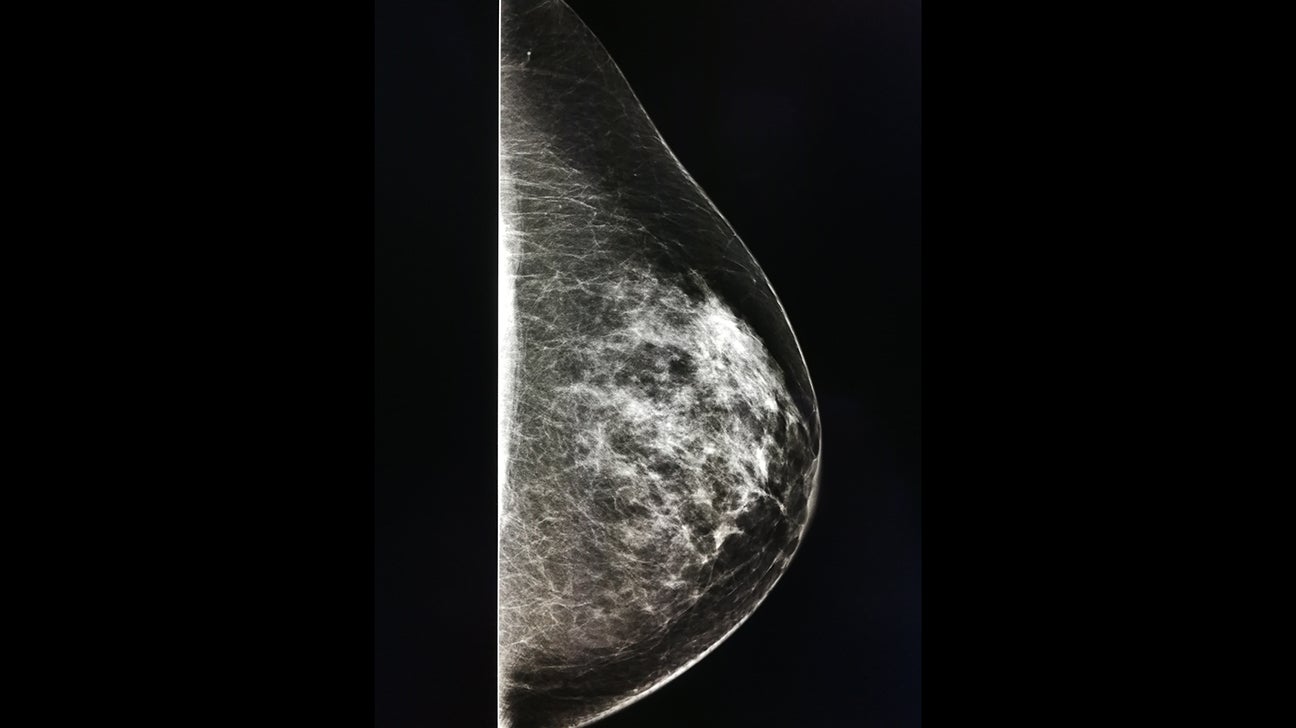

They appear as white spots or flecks on a mammogram but can't be felt during a breast exam. A new group has formed. For women treated for breast cancer in the past, calcifications may also be due.

There are numerous causes for calcium deposits in the breasts, including: But, japanese food natto has the ability to decalcify and maintain uniform level of calcium throughout the body and parts. Breast calcifications. california pacific medical center: